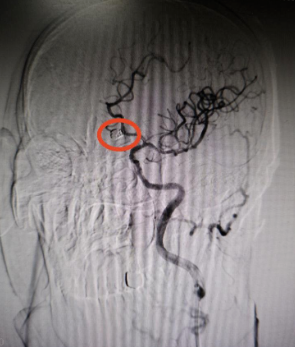

动脉瘤栓塞术后:可见动脉瘤致密栓塞,支架内血流通畅